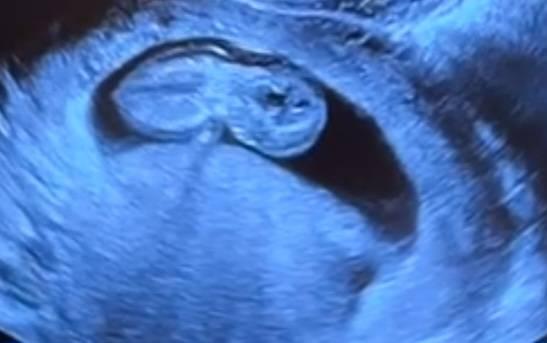

Hallo! Leider weiß ich nicht ob ich in diesem Forum richtig bin! Bin heute 10+4, SLL 3,7 cm Frauenärztin sagt wäre ok Nackenfalte 2.6, solle ich dringend abklären lassen, am besten in der nächsten Woche, ich bekomme nirgends einen Termin Habe mir zuhause das Ultraschallbild genauer angesehen und das ganze Bild ist irgendwie eine schlechte Qualität denk ich! Plötzlich sieht die fruchthöhle 2 geteilt aus, aber nur in der einen Hälfte liegt ein Baby. Das Baby hat komische schwarze Flecken im Kopf (liegt auf der seite) und wenn man direkt auf Gesicht sieht, sieht es aus wie ein Gespenst?? Die Augen??? Meinen Mann und mich beunruhigt das total. 2te Meinung einholen? Bin total überfordert und so traurig :( habe 2 Jahre dafür gebraucht und jetzt sowas :(

Bild zu 11 Schwangerschaftswoche - Ultraschall - Schwanger - wer noch? Rund um die Schwangerschaft

Bild von vorne denk ich

So sieht dein Baby ja nicht aus ... Das sind ja nur Ultraschall Schatten. Die Nackenfalte ist im Nacken... die sieht man auf dem Bild.... Ich finde sie auch nicht extrem, aber das muss natürlich ein Facharzt beurteilen. Deswegen ist das Kind von hinten seitlich abgebildet. Das Gesicht zeigt nach unten und die Hand hat es vor den Gesicht. Die schwarzen Punkte haben also erstmal nichts zu bedeuten... Du bekommst kein kleines Spukgespenst wie es für dich auf den Bild vielleicht aussieht. Bleib ruhig Hast du bei der Feindiagnostik angerufen? Ich habe da eigentlich recht zügig ein Termin bekommen.